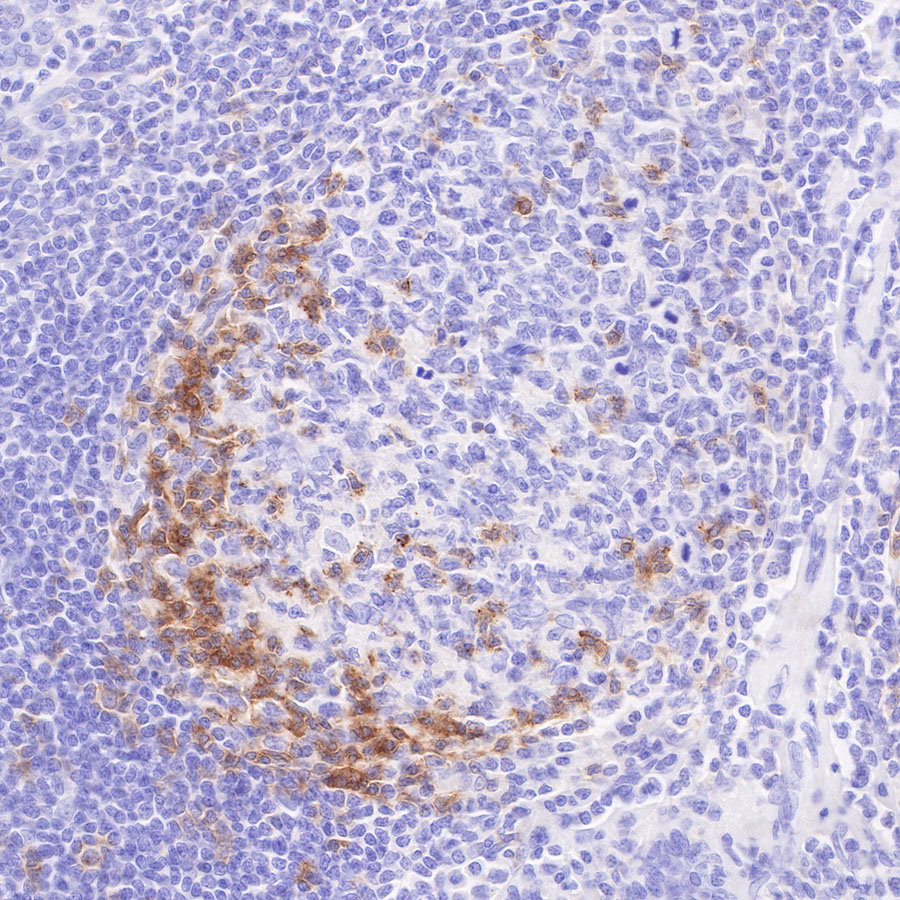

Immunohistochemistry

IHC shows positive staining in paraffin-embedded human tonsil. Anti-PD-1 antibody was used at 1/200 dilution, followed by a HRP Polymer for Mouse & Rabbit IgG (ready to use). Counterstained with hematoxylin. Heat mediated antigen retrieval with Tris/EDTA buffer pH9.0 was performed before commencing with IHC staining protocol.

IHC shows positive staining in paraffin-embedded human spleen. Anti-PD-1 antibody was used at 1/500 dilution, followed by a HRP Polymer for Mouse & Rabbit IgG (ready to use). Counterstained with hematoxylin. Heat mediated antigen retrieval with Tris/EDTA buffer pH9.0 was performed before commencing with IHC staining protocol.